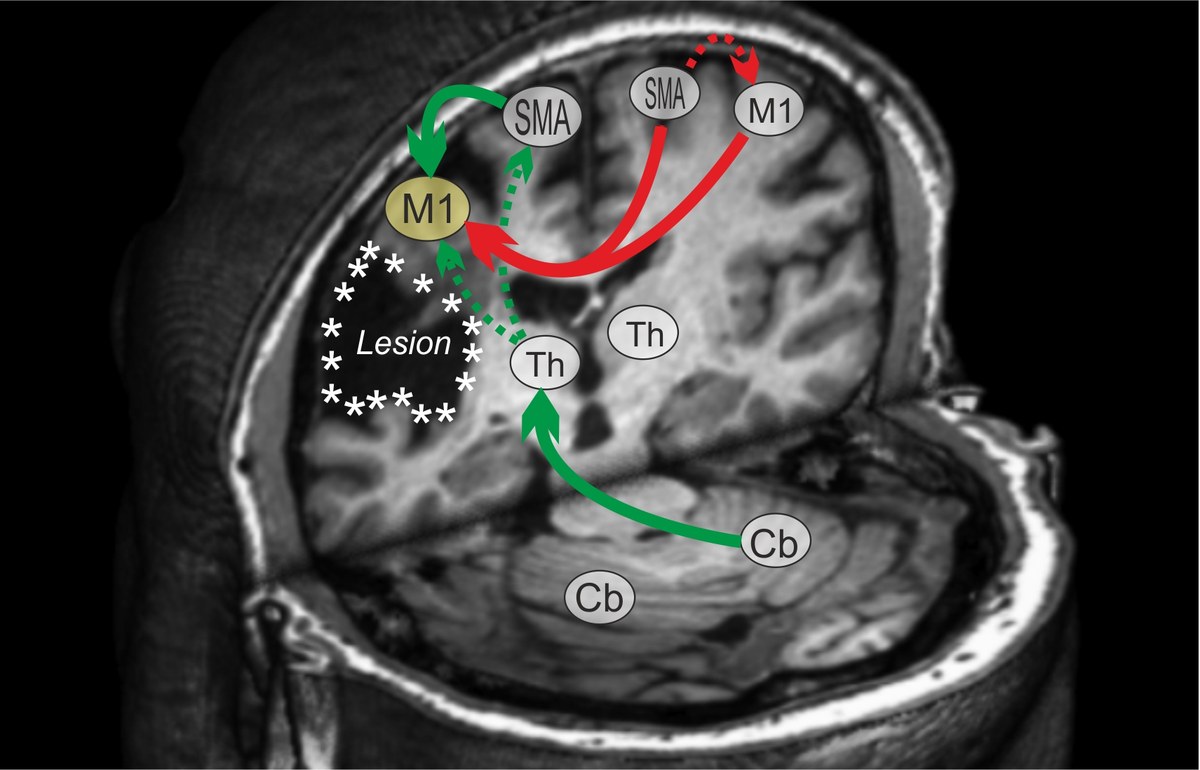

Ein zentrales Ziel unserer Forschungsarbeiten ist herauszufinden, welche Hirnregionen essentiell sind für eine erfolgreiche Funktionserholung und wie durch nicht-invasive Hirnstimulation die Reorganisationsprozesse hierfür unterstützt werden können.

Wir kombinieren moderne Bildgebungsmethoden (strukturelle/ funktionelle MRT) mit elektrophysiologischen Verfahren (Elektroenzephalographie) und nicht-invasiver Hirnstimulation (transkranielle Magnetstimulation (TMS), repetitive TMS; pharmakologische Stimulation), um neurale Plastizität zu verstärken und die Funktionserholung zu fördern.